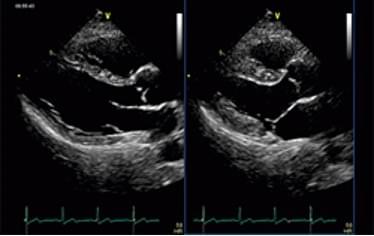

心臓超音波検査

心臓の形態や血流情報を直接超音波で画像化することで、より精密な心臓検査が可能です。心筋梗塞、弁膜症、心筋症、心肥大などの診断をいたします。心電図異常や心雑音を指摘された方には、非常に有用な検査です。